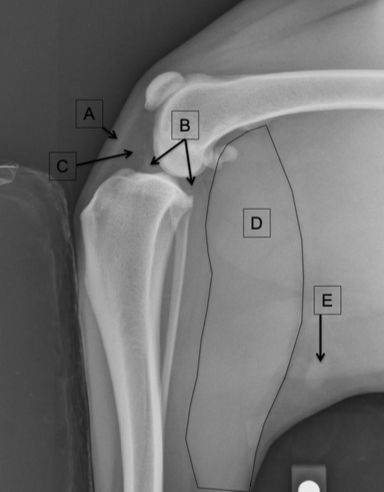

Label the structures

A

A = patella

B = distal femur

C = fabellae

D = tibia

E = fibula